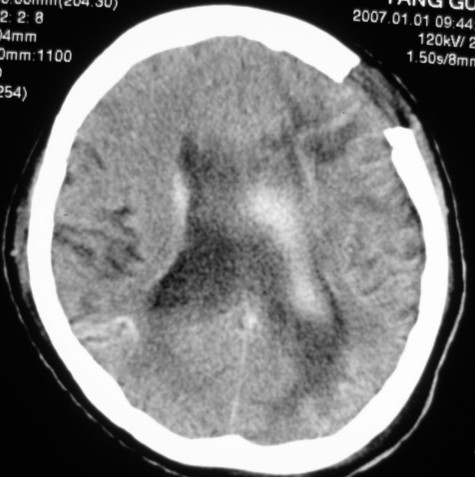

标题: CT9218:男性,50岁,脑出血术后复查,两次片相隔半月,请分 [打印本页]

标题: CT9218:男性,50岁,脑出血术后复查,两次片相隔半月,请分

第一次ct片脑出血术后,出血吸收期。第二次ct 片左颞顶枕部及右颞顶部有脑回样高密度影。考虑珠网膜下腔出血。脑出血术后改变,脑出血恢复期 并脑积水。

第一次ct片脑出血术后,出血吸收期。第二次ct 片左颞顶枕部及右颞顶部有脑回样高密度影。考虑珠网膜下腔出血。脑出血术后改变,脑出血恢复期 并脑积水